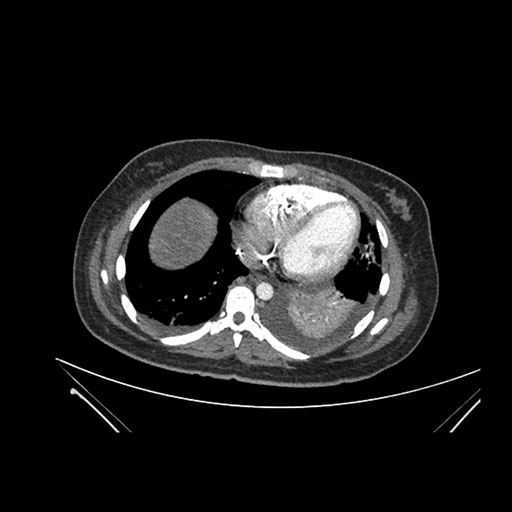

Axial Arterial